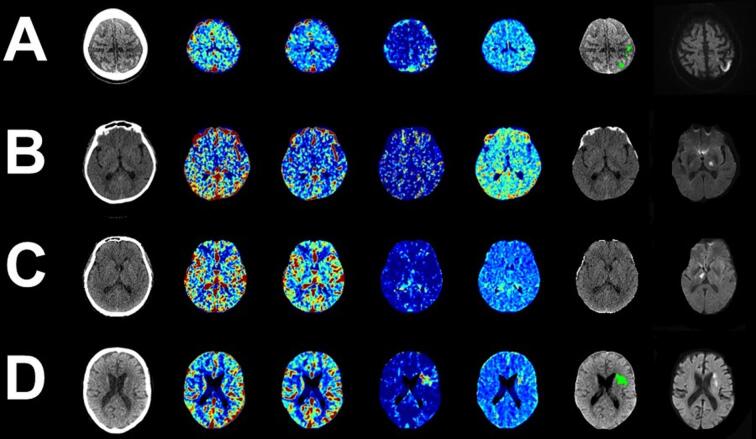

Posterior circulation infarction (POCI) is common. Imaging techniques such as non-contrast-CT (NCCT) and diffusion-weighted-magnetic-resonance-imaging commonly fail to detect hyperacute POCI. Studies suggest expert inspection of Computed Tomography Perfusion (CTP) improves diagnosis of POCI. In many settings, there is limited access to specialist expertise. Deep-learning has been successfully applied to automate imaging interpretation. This study aimed to develop and validate a deep-learning approach for the classification of POCI using CTP.

Data were analysed from 3541-patients from the International-stroke-perfusion-registry (INSPIRE). All patients with baseline multimodal-CT and follow-up imaging performed at 24–48 h were identified. A cohort of 541-patients was constructed on a 1:3 POCI-to −reference-ratio for model analysis. A 3D-Dense-Convolutional-Network (DenseNet) was trained to classify patients into POCI or non-POCI using CTP-deconvolved-maps. Six-stroke-experts also independently classified patients based upon stepwise access to multimodal CT (mCT) data. DenseNet results were compared against expert clinician results. Model and clinician performance was evaluated using area-under-the-receiver-operating-curve, sensitivity, specificity, accuracy and precision. Clinician agreement was measured with the Fleiss-Kappa-statistic.

Best mean clinician diagnostic accuracy, sensitivity and agreement was demonstrated after review of all mCT data (AUC: 0.81, Sensitivity: 0.65, Fleiss-Kappa-statistic: 0.73). There was a spectrum of individual clinician results with an AUC-range of 0.73–0.86. Best DenseNet performance was recorded with an input combination of NCCT and delay-time maps. The DenseNet model was superior to the best mean clinician performance (AUC: 0.87) and was due to enhanced sensitivity (DenseNET: 0.77, Clinician: 0.65). The degree to which the DenseNet model outperformed each clinician ranged and was clinician specific (AUC improvement 0.01–0.14).